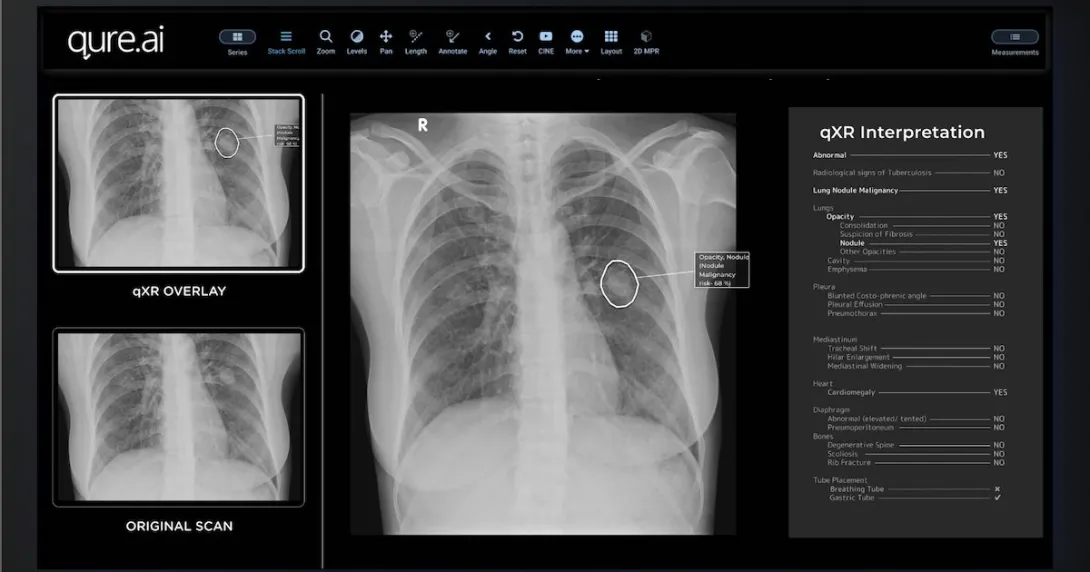

Qure.ai's qXR software will enable Mylab's upcoming x-ray device to quickly detect TB.

Photo courtesy of Qure.ai

Indian biotech company Mylab Discovery Solutions is integrating Qure.ai's AI technology into its upcoming x-ray device for screening tuberculosis.

According to a press statement, MyBeam is a compact, lightweight device equipped with high-frequency technology for detecting TB. It will be powered by Qure.ai's deep-learning software qXR to analyse chest x-ray images and identify TB within a minute.